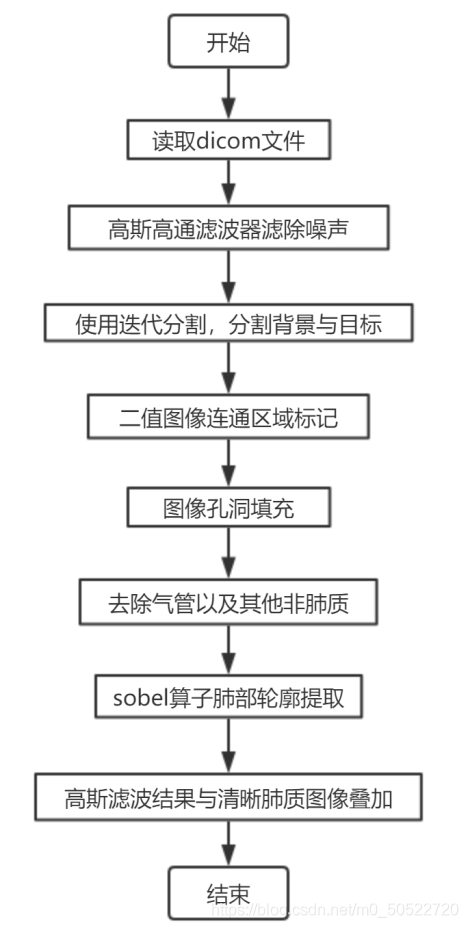

胸部CT图像中肺部提取,轮廓跟踪技术勾画出肺部轮廓

1、实验步骤

2、实验过程

(1)dicom文件的读取

dicom是委员会开发的用于成像设备之间进行通信的标准。使用dicomread函数读取dicom文件,并显示原始横截面胸部 HRCT 层片。

本文介绍如何通过dicom文件读取、高斯滤波、迭代分割等步骤,利用轮廓跟踪技术在胸部CT图像中提取肺部轮廓,包括噪声过滤、二值化处理、肺质填充、气管消除及边缘提取等关键步骤,适用于医疗影像分析与计算机视觉研究。

本文介绍如何通过dicom文件读取、高斯滤波、迭代分割等步骤,利用轮廓跟踪技术在胸部CT图像中提取肺部轮廓,包括噪声过滤、二值化处理、肺质填充、气管消除及边缘提取等关键步骤,适用于医疗影像分析与计算机视觉研究。